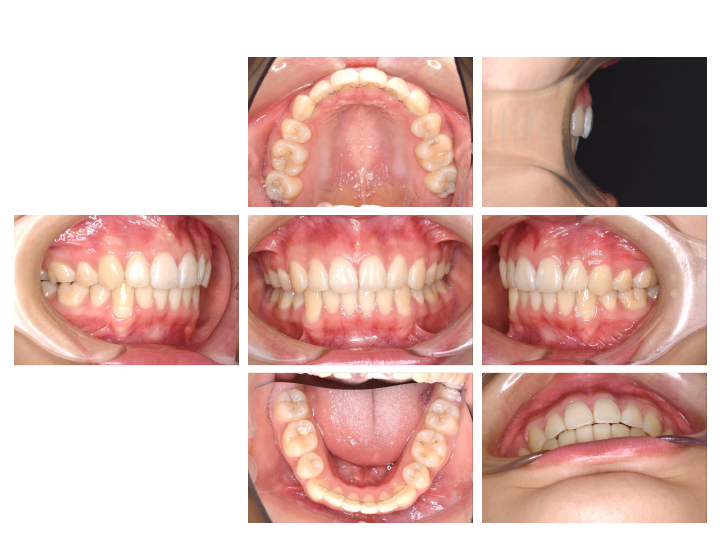

実は小児矯正とはいっても、一般的には成人矯正までかかることが多くあります。

日本の小児矯正のおよそ7割は、成人の抜歯矯正になるため、期間にすると、矯正を始めてからおよそ10年かかることになります。

小学生から始めて大学生までかかる長期治療となります。

ですが、当院の「骨格にフォーカスした矯正」ならほとんどが小児矯正(およそ2年)で終わります。